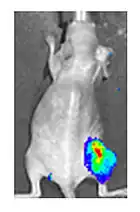

Viral luciferase expression in a mouse tumour

Both in the laboratory and in the clinic it is useful to have a simple means of identifying cells infected by the experimental virus. This can be done by equipping the virus with "reporter genes" not normally present in viral genomes, which encode easily identifiable protein markers. One example of such proteins is GFP (green fluorescent protein) which, when present in infected cells, will cause a fluorescent green light to be emitted when stimulated by blue light.[89][90] An advantage of this method is that it can be used on live cells and in patients with superficial infected lesions, it enables rapid non-invasive confirmation of viral infection.[91] Another example of a visual marker useful in living cells is luciferase, an enzyme from the firefly which in the presence of luciferin, emits light detectable by specialized cameras.[89]